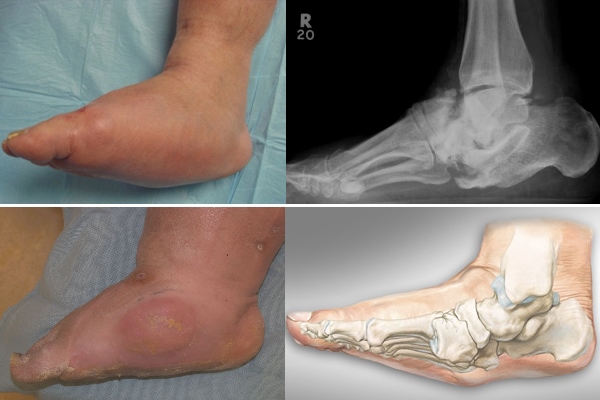

Первая стадия часто остается незамеченной, даже при инструментальной диагностике. На рентгеновских снимках видны лишь незначительные изменения, а дискомфорт при ходьбе отсутствует.

На начальных этапах заболевания могут наблюдаться легкие отеки, покраснение кожи и повышение температуры в области пораженного сустава.

На подострой стадии отек поврежденной конечности усиливается. Рентгенограмма показывает деформацию костей стопы, в суставе появляется хруст и боль при движении.

Для второй стадии характерны заметные различия между здоровой и пораженной ногами, а также уплощение пострадавшей стопы.

На хронической стадии деформация стопы становится очевидной даже без специального оборудования. Происходит вальгусная деформация, при которой ось пятки искривляется и заваливается внутрь.

Основным методом диагностики стопы Шарко на всех стадиях заболевания является рентгенография. Исследование проводится в прямой и боковой проекциях. Рентгеновские снимки помогают выявить снижение костной плотности и степень деформации.